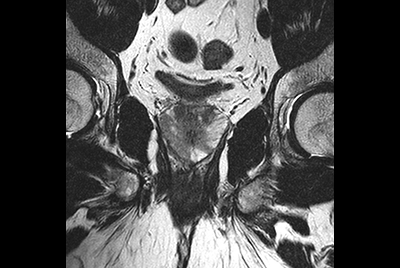

Prostate with dual coil set-up